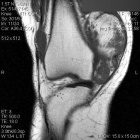

V.D. - 51 year old woman with intermittent right knee pain and swelling after twisting it three years ago

Zoom image: Radiological image Radiological image.